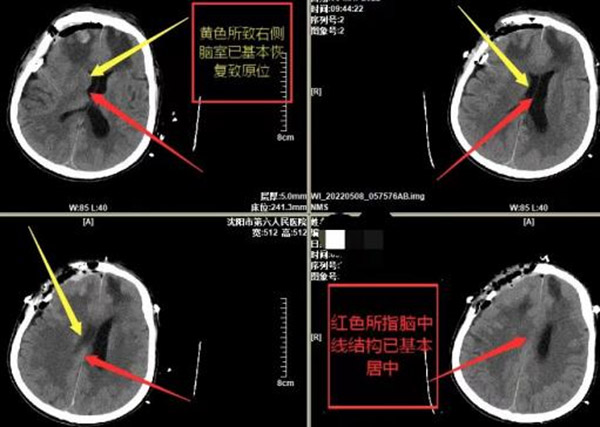

两周后的一天,正在家休养的张先生突发意识不清,他的妻子曾在抖音上看到过沈阳六院神经外科闻华主任的介绍,因此情急下张先生的家人将他送到沈阳市第六人民医院急诊科,复查头颅CT提示,脑挫裂伤加重,有新发出血,脑水肿较前加重,中线结构向左移位,脑疝形成,随时有生命危险。

(患者术后头CT)

术后张先生被送到神经外科过渡病房进行进一步治疗,另一边,核酸结果回报是阴性,张先生在疫情防控下获得了最佳的抢救时机。“目前患者的意识很清楚,能够进行语言交流,四肢活动自如,一周后可以下地活动”,闻华主任介绍。